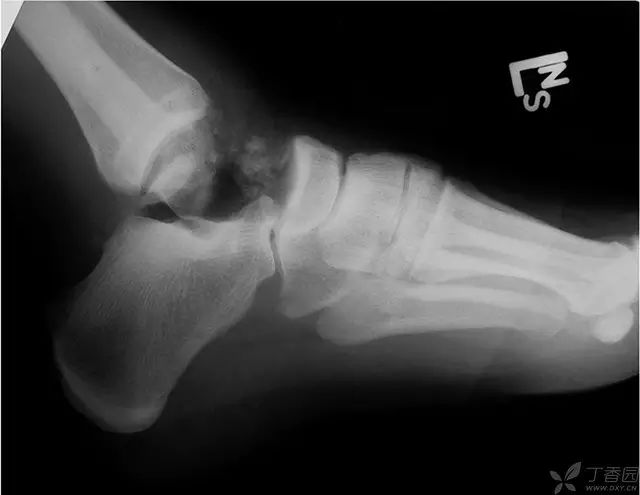

病例一[3]

39 岁男性,体重 131 Kg,身高 190 cm,卡车司机,车祸伤。救护车上无菌冰袋包裹游离距骨入院,入院后改用冰的头孢唑林溶液浸泡

急诊手术清创,9L 生理盐水充分灌洗创口;生理盐水及头孢唑林溶液浸泡以后,直接回植,克氏针临时固定,伤口覆盖抗生素链珠,保持开放。受伤到回植的时间为 4 小时。

72 小时后再次清创灌洗,拔除克氏针关闭创口。术后抗菌药物治疗 7 天,10 天后出院,无术后早期并发症。10 周后部分负重,15 周后完全负重。

2-5 年 X 线片,可见距下关节、胫距关节关节炎。距骨体逐渐出现硬化,无塌陷